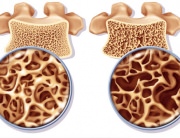

The bones of people suffering from osteoporosis are thin and very fragile. “Osteo” comes from the Greek “osteon”, which means “bone”, while “porosis” comes from the Greek word “poros”, meaning “hole, passage”. According to the medical dictionary Medilexicon, osteoporosis is a “Reduction in the quantity of bone or atrophy of skeletal tissue; an age-related disorder characterized by decreased bone mass and loss of normal skeletal microarchitecture, leading to increased susceptibility to fractures”.

German scientists have brought to light a molecular mechanism that adjusts the balance between bone formation and resorption. They were able to show that two different forms of a regulating gene – a short and a long isoform – determine this process. Osteoporosis is a disease that causes the fragility of the bones, leading to an increased risk of fractures (breaks or fissures) than in the case of healthy bones.

Osteoporosis occurs when the bones lose minerals, such as calcium, faster than it can replace it; this leads to a bone thickness decrease (the decrease of the bone mass or density). As a result, the bones become thinner and lose their density, so that the slightest impact or accident can lead to severe consequence fractures. They are also called minor trauma fractures or fragility fractures.